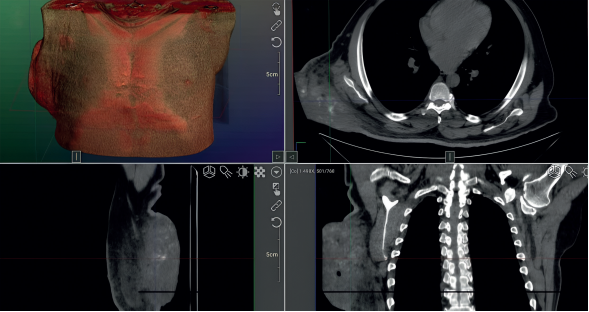

La tomografía evidenció una lesión de gran tamaño con densidad de tejidos blandos, ubicada en la región dorsal derecha y extendida hacia la línea axilar posterior (figura 2). Además, se observó afectación ganglionar ipsilateral (figura 3).

Imágenes: Calderón Valderrama, et al.

Figura 2 Tomografía axial de tórax en fase simple, ventana para mediastino, que revela una gran lesión exofítica de densidad de tejidos blandos, localizada en la región dorsal derecha, en la línea axilar posterior. a) Reconstrucción volumétrica. b) Proyección axial. c) Reconstrucción sagital. c) Coronal.

Figura 3 a) Tomografía axial de tórax en fase simple en plano axial. b) Reconstrucción coronal, ambas en ventana para tejidos blandos, donde se observan ganglios axilares con pérdida de su morfología habitual, en relación con la infiltración del tumor primario ya diagnosticado.